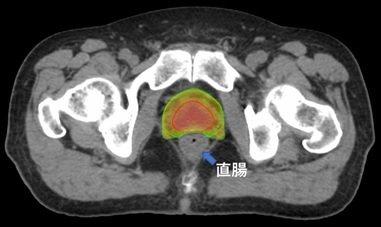

併存疾患のため手術できず薬物療法と放射線治療の併用療法で根治を目指した。

IMRTを用いて直腸がん自体には高線量を、転移しやすいリンパ節領域には予防的な線量を照射。